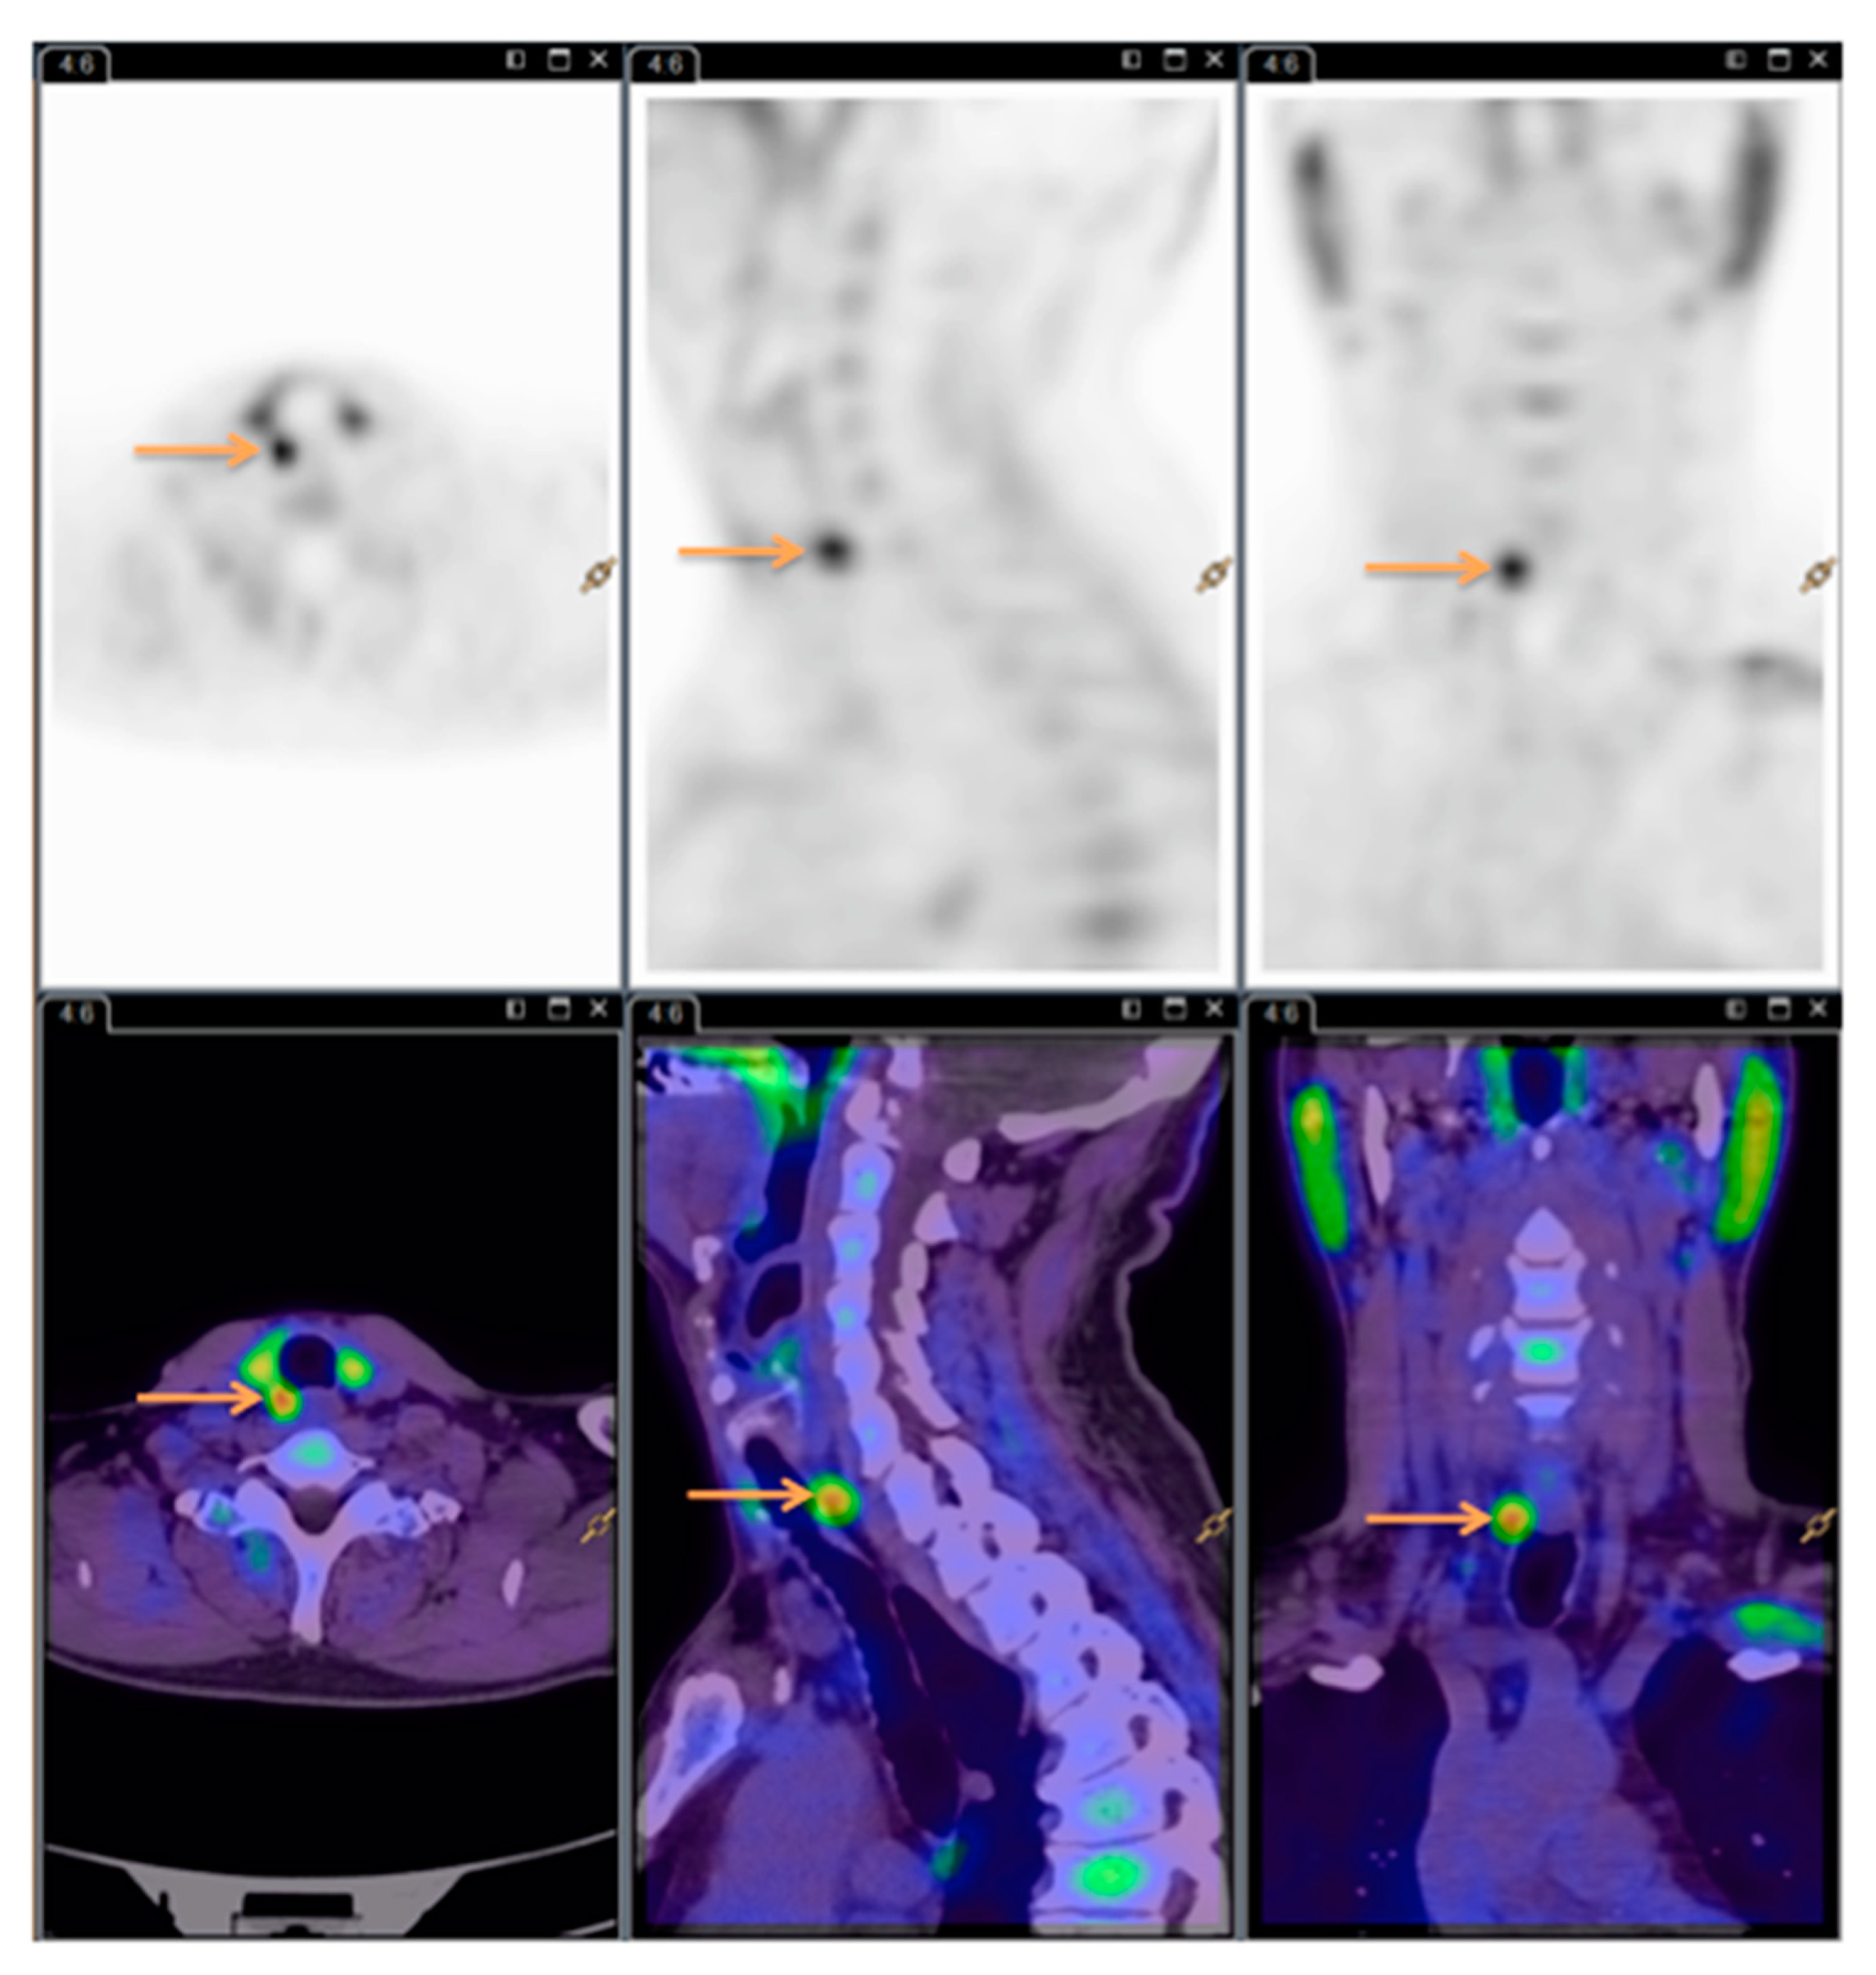

All the 11C-Choline PET/CT scans were read by the same experienced nuclear medicine specialist. See Figure 3 for images (same patient as Figure 1 and Figure 2).

Figure 3. 11C-Choline Positron emission tomography/computed tomography (PET/CT). Arrows showing the hyperfunctioning parathyroid gland.